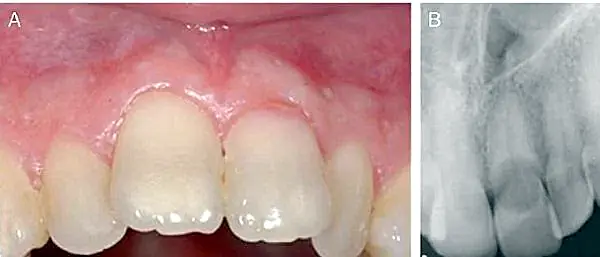

- Mancha rosada en tercio cervical de la corona dentaria (ver figura 1).

Figura 1. A. Coloración rosada en tercio cervical del 2.1 (Imagen radiográfica (Patel, 2009)